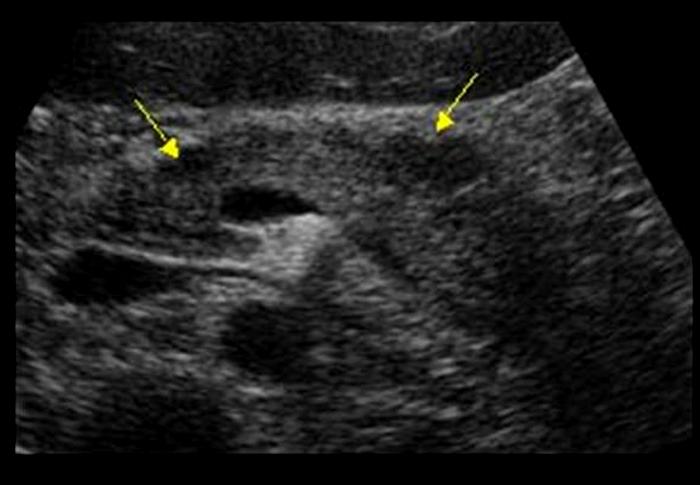

Chronic Pancreatitis

Ongoing inflammation that results in permanent damage

N & V

flatulence

weight loss

Chronic Pancreatitis

Ongoing inflammation that results in permanent damage